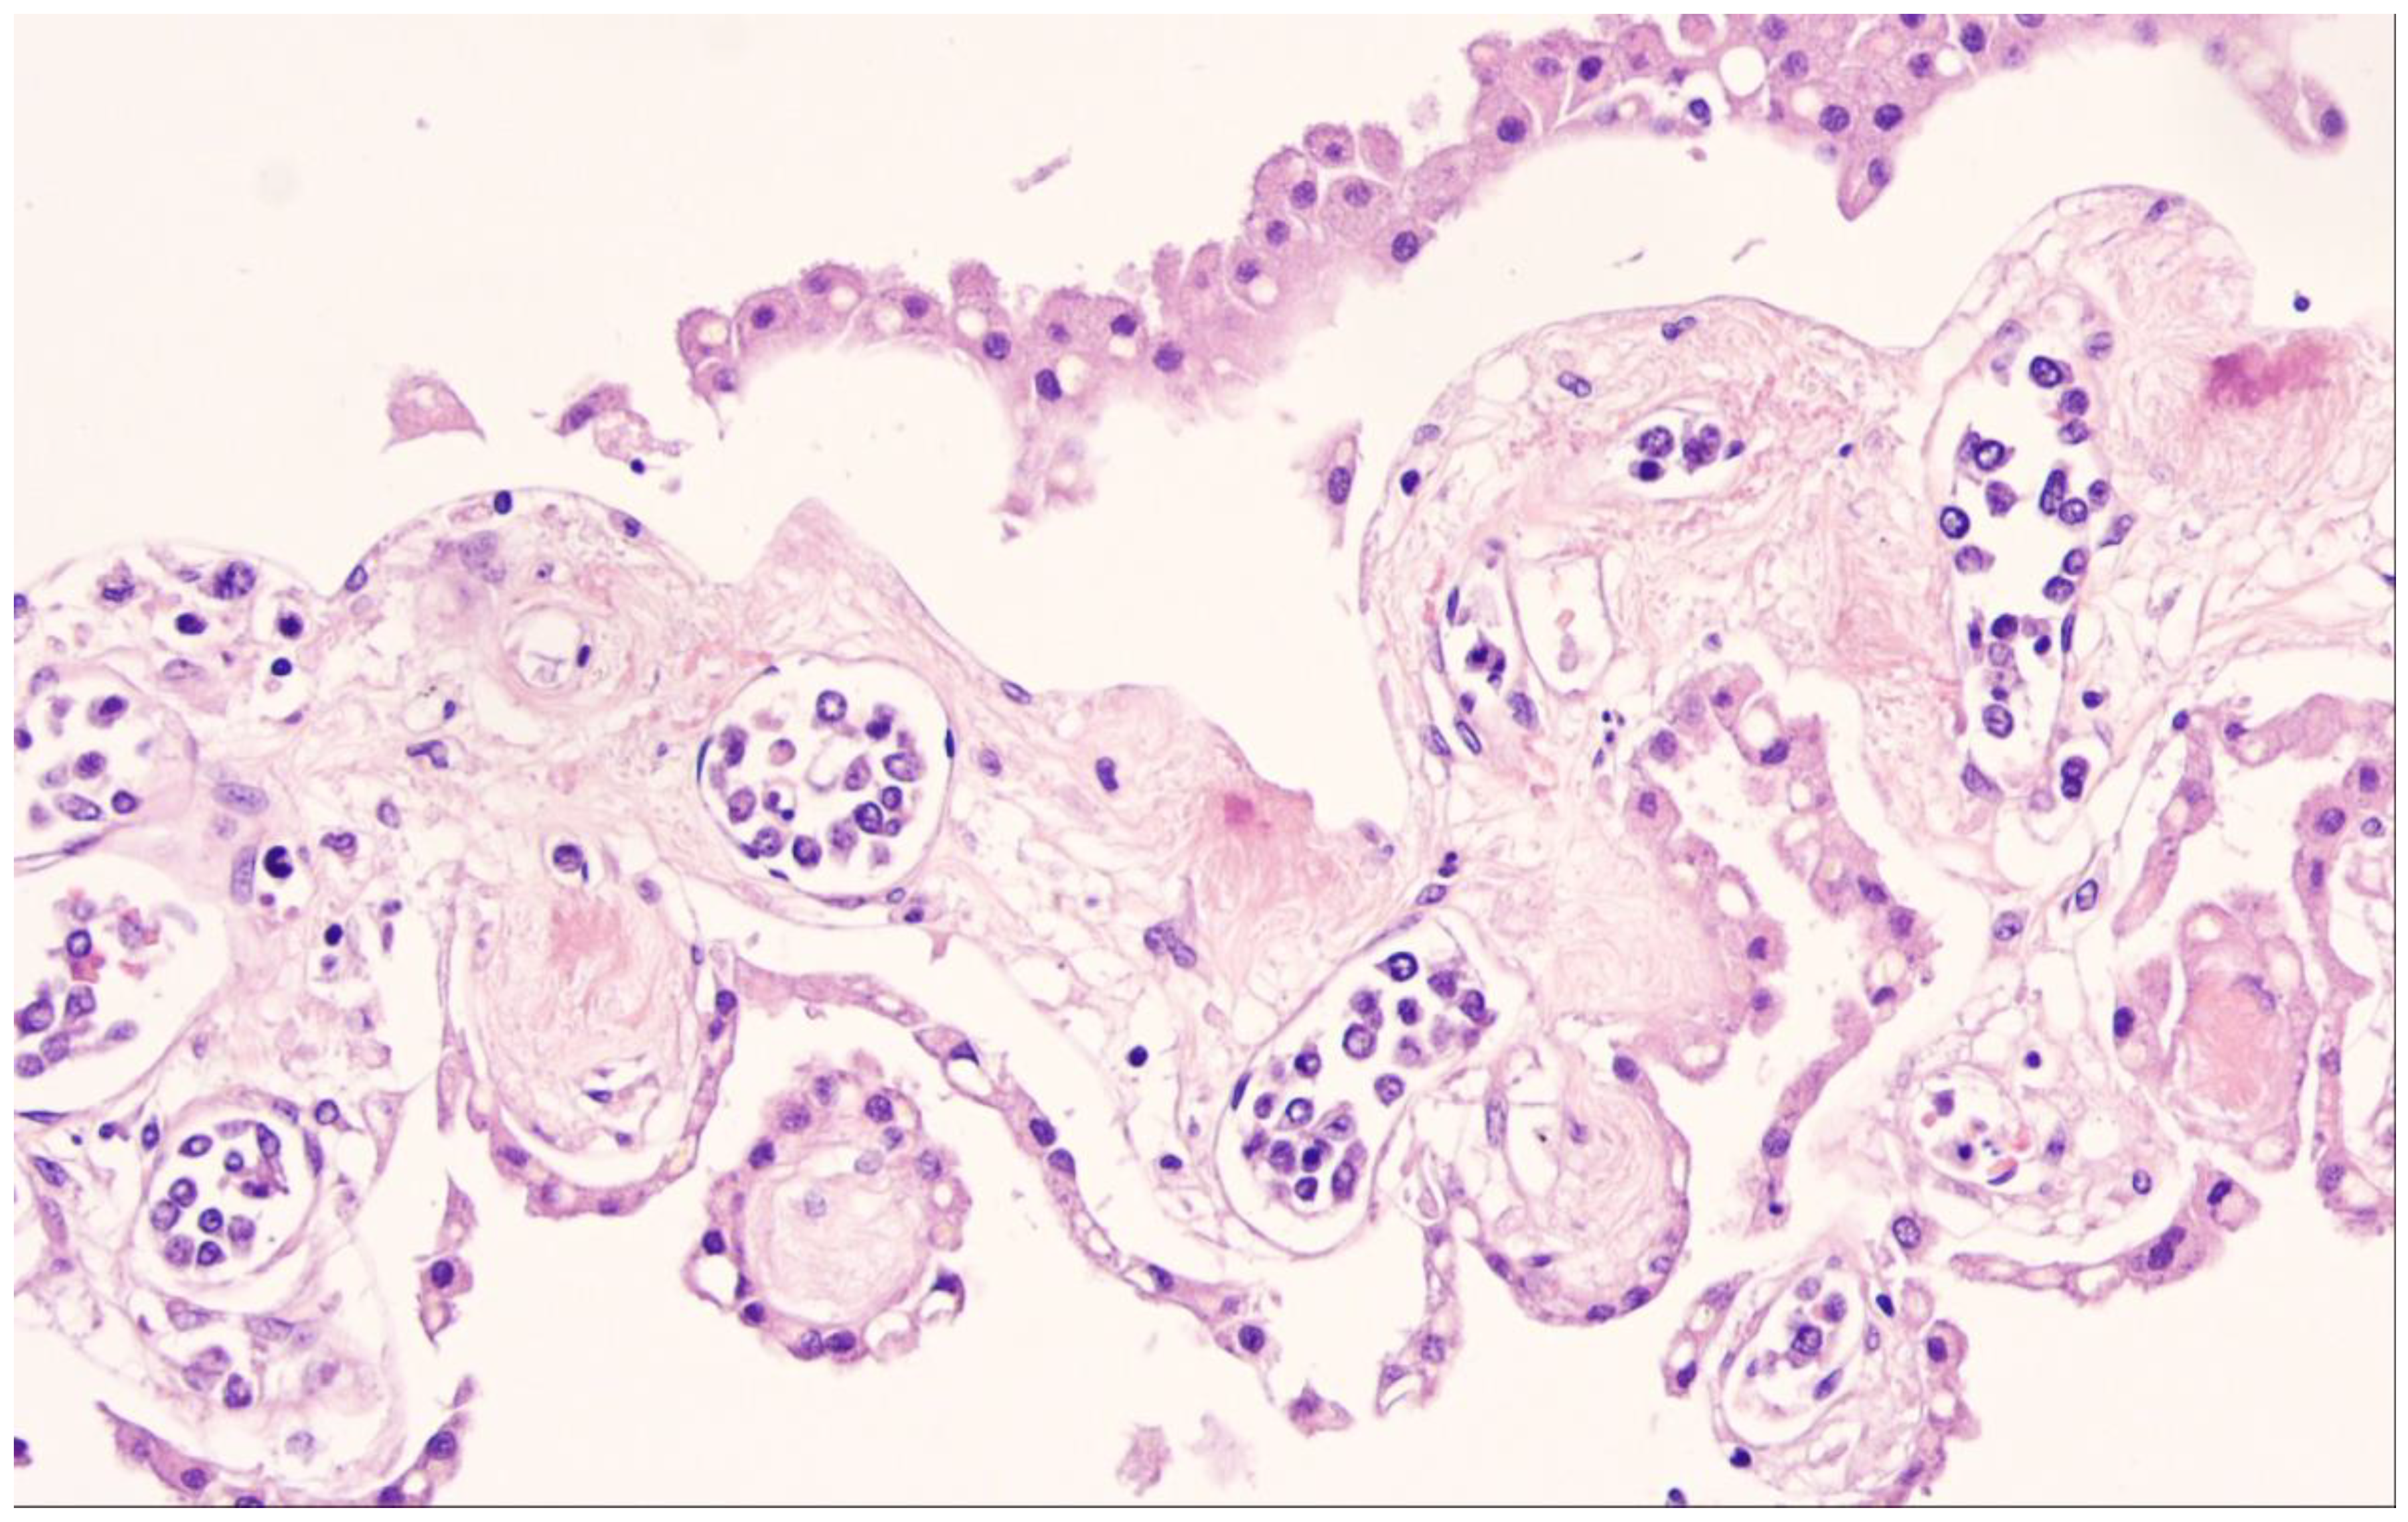

9. Lymphomatoid Granulomatosis

- Katzenstein, A.L.; Doxtader, E.; Narendra, S. Lymphomatoid granulomatosis: Insights gained over 4 decades. Am. J. Surg. Pathol. 2010, 34, e35–e48. [Google Scholar] [CrossRef]

- Song, J.Y.; Pittaluga, S.; Dunleavy, K.; Grant, N.; White, T.; Jiang, L.; Vies-Hill, T.; Raffeld, M.; Wilson, W.H.; Jaffe, E.S. Lymphomatoid granulomatosis—A single institute experience: Pathologic findings and clinical correlations. Am. J. Surg. Pathol. 2015, 39, 141–156. [Google Scholar] [CrossRef] [PubMed]

- Chavez, J.C.; Sandoval-Sus, J.; Horna, P.; Dalia, S.; Bello, C.; Chevernick, P.; Sotomayor, E.M.; Sokol, L.; Shah, B. Lymphomatoid Granulomatosis: A Single Institution Experience and Review of the Literature. Clin. Lymphoma Myeloma Leuk. 2016, 16, S170–S174. [Google Scholar] [CrossRef] [PubMed]

- Sordillo, P.P.; Epremian, B.; Koziner, B.; Lacher, M.; Lieberman, P. Lymphomatoid granulomatosis: An analysis of clinical and immunologic characteristics. Cancer 1982, 49, 2070–2076. [Google Scholar] [CrossRef]

- Wilson, W.H.; Kingma, D.W.; Raffeld, M.; Wittes, R.E.; Jaffe, E.S. Association of lymphomatoid granulomatosis with Epstein-Barr viral infection of B lymphocytes and response to interferon-alpha 2b. Blood 1996, 87, 4531–4537. [Google Scholar] [CrossRef] [PubMed]

- Teruya-Feldstein, J.; Jaffe, E.S.; Burd, P.R.; Kanegane, H.; Kingma, D.W.; Wilson, W.H.; Longo, D.L.; Tosato, G. The role of Mig, the monokine induced by interferon-gamma, and IP-10, the interferon-gamma-inducible protein-10, in tissue necrosis and vascular damage associated with Epstein-Barr virus-positive lymphoproliferative disease. Blood 1997, 90, 4099–4105. [Google Scholar] [CrossRef]